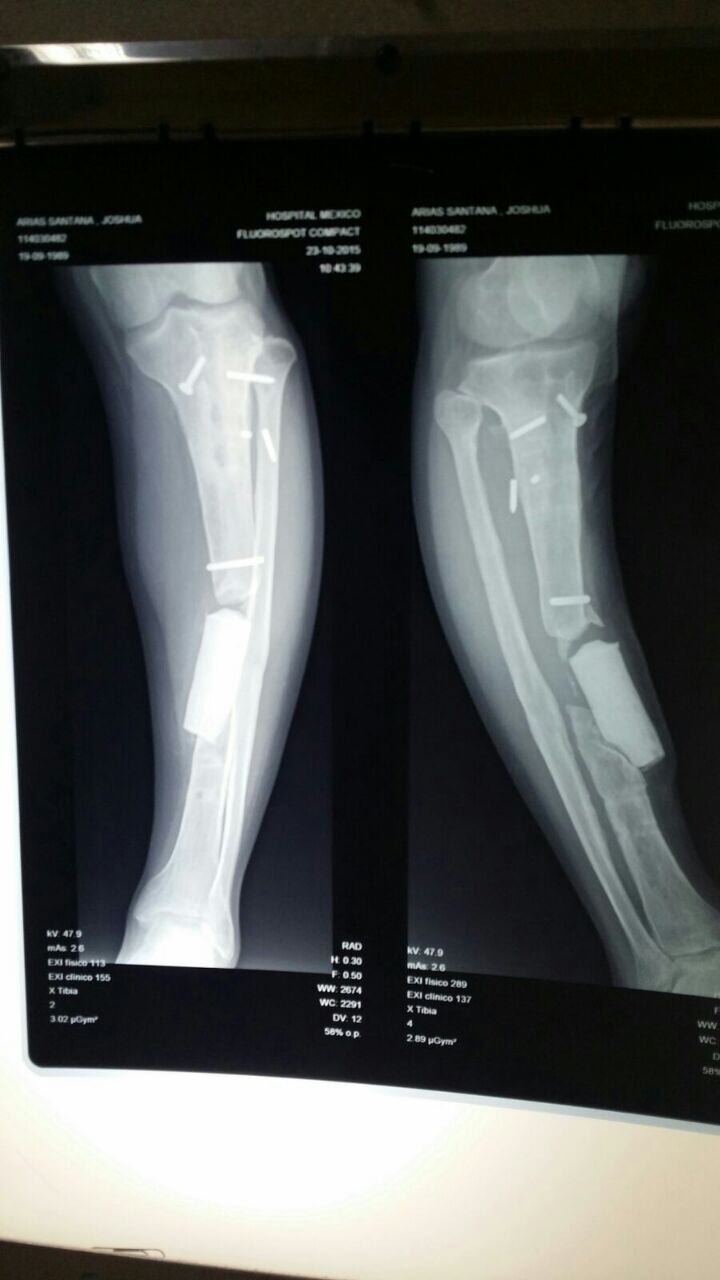

Segundos después, que parecieron horas para Joshua, cayó a la arena y cuando quiso levantarse para irse corriendo se dio cuenta que tenía la pierna quebrada, había sufrido una gravísima lesión de tibia y peroné que fue el arranque de una pesadilla que consistió en 19 operaciones y una amputación siete años después, luego de muchos intentos por salvar la pierna.

“Fue el proceso más largo y duro de mi vida, jamás pensé que esto podía llegar a tanto, toda la vida he sido deportista, creí que no sería nada, me pusieron un pin de la rodilla y tobillo y no pegó, fueron tres meses en los que lloraba día y noche, yo pensé que era que no aguantaba nada más. Pasé cirugía tras cirugía teniendo la esperanza de recuperarme, jamás me vi con una pierna menos y la primera vez que un doctor me dijo que existían fantasmas de una amputación quedé en shock y dije que no, que a mí nadie me iba a cortar una pierna, es mía, no suya le respondí al doctor”, relató.